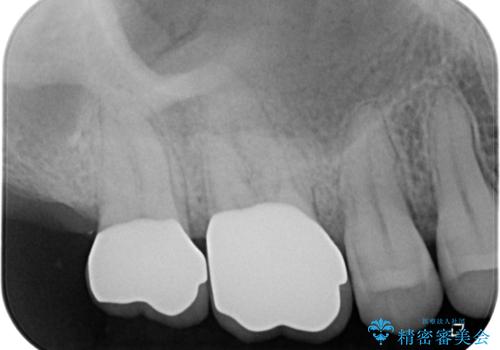

- むし歯治療途中で放置していた奥歯から、歯磨きの度に出血するとのことで来院された患者様です。

隣接する部分の間のむし歯が歯肉の奥深くにまで及んでおり、歯肉が腫れやすい状態となっていたため、歯肉の切除並びに歯槽骨の形態修正を行い、虫歯が歯肉の外に出てくるようにした上で、オールセラミックにて補綴することとしました。